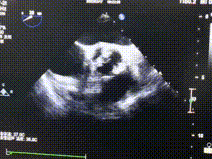

超声评估:

术前超声:L-R窦之间融合,大量反流

术后超声:瓣膜植入位置良好、形态完整,反流消失